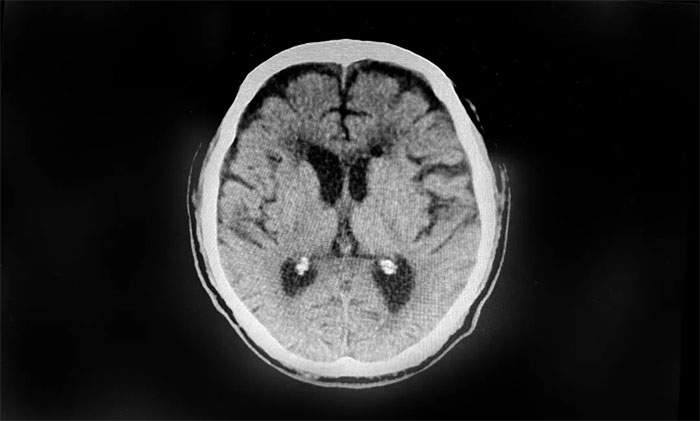

行颅脑CT检查,患者双侧额颞枕顶部可见硬膜下积液血肿,双侧额叶受压明显,不排除积液血肿进一步加重。若不及时手术治疗,病情可能进一步恶化,甚至可能危及生命。

▲ 患者双侧额顶部硬膜下积液血肿明显